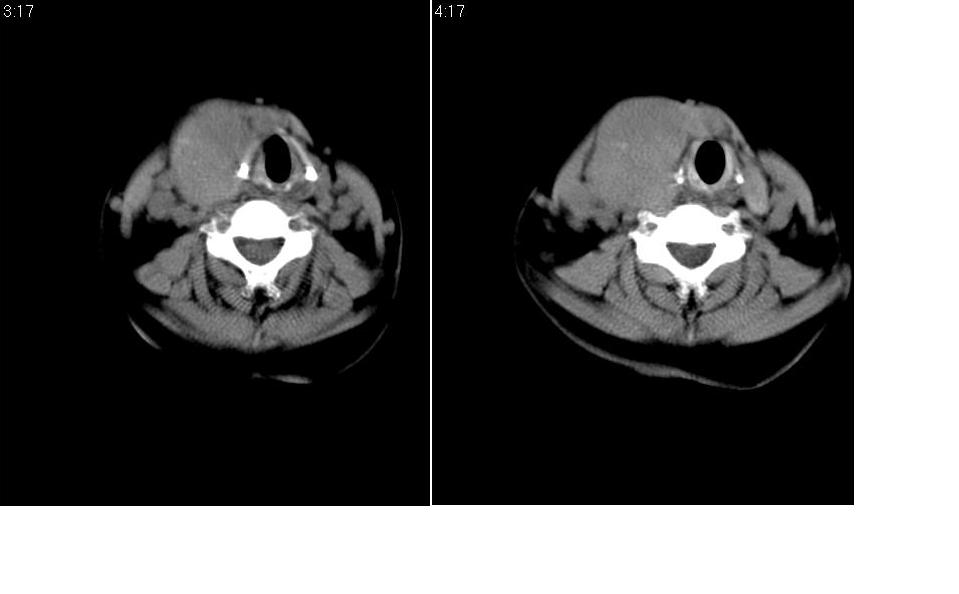

标题: CT27207:颈部CT平扫

女 55岁 右侧颈部包块十年余,自己感觉有增大。

边缘清晰光滑,偏向于甲状腺瘤。

来源于右侧甲状腺  边界清晰,内可见点状钙化,向下生长达前上纵隔血管间隙内  考虑甲状腺腺瘤并胸内甲状腺肿

甲状腺瘤可能性大!建议强化!